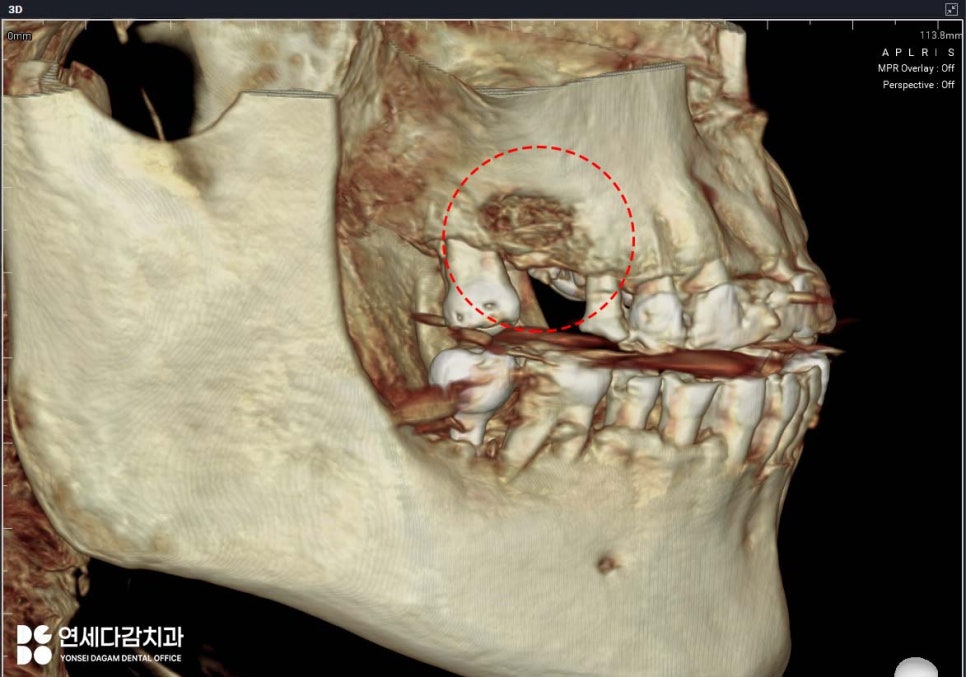

측방 접근법

(Lateral Approach)

치조정이 아닌 상악골 측면에 창을 형성하여

막에 직접 접근합니다.

잇몸을 절개하여 뼈를 드러낸 후

골 측벽에 타원형의 골창을 형성합니다.

이 창을 통해 눈으로 직접 보며

막을 조심스럽게 박리하여 들어 올립니다.

장점은 눈으로 확인하면서

거상할 수 있어 문제 발생 시

즉각 대처가 가능합니다.

또한 거상량에 제한이 적어

10mm 이상의 거상도 가능하고

충분한 양의 뼈이식재를 채울 수 있습니다.

오금역 치과 에서는

잔존골이 3mm 이하로 극히

부족한 경우에 적용할 때가 많습니다.